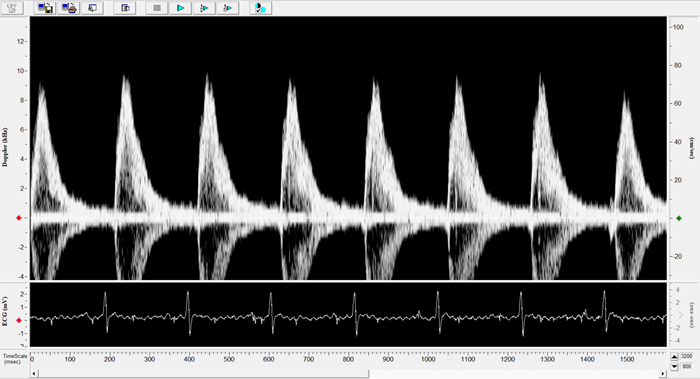

Rat - Abdominal Aorta

Rat - Abdominal Aorta. Image Credit: Scintica Instrumentation Inc.